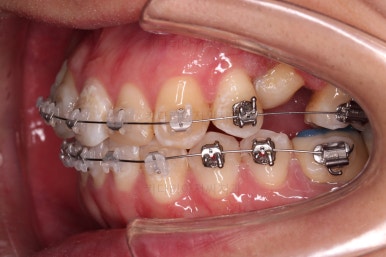

장치를 부착한 모습입니다.

이번 환자분은 자가결찰 세라믹(엠파워 클리어) 장치를 선택하셨고요.

잔존유치는 발치했고, 앞니 가짜치아는 벗겨내고 새로운 가짜치아를 와이어에 묶어주었습니다.

매복 영구치도 거의 다 배열되어 가고요.

임플란트 공간도 많이 확보되었습니다.

임플란트를 위한 기본 셋팅이 거의 완료되었습니다.

이 모습까지 13개월 걸렸네요.